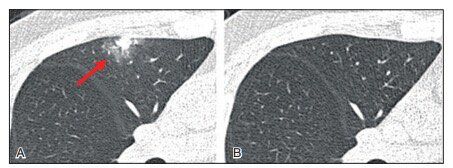

▲图2 患者男性,47岁。良性纯 GGO 结节。A.薄层CT扫描显示右上肺叶一个7 mm的纯结节GGO;B.薄层CT显示病变6个月后不减少或不消失。病理检查示局灶性肺间质纤维化